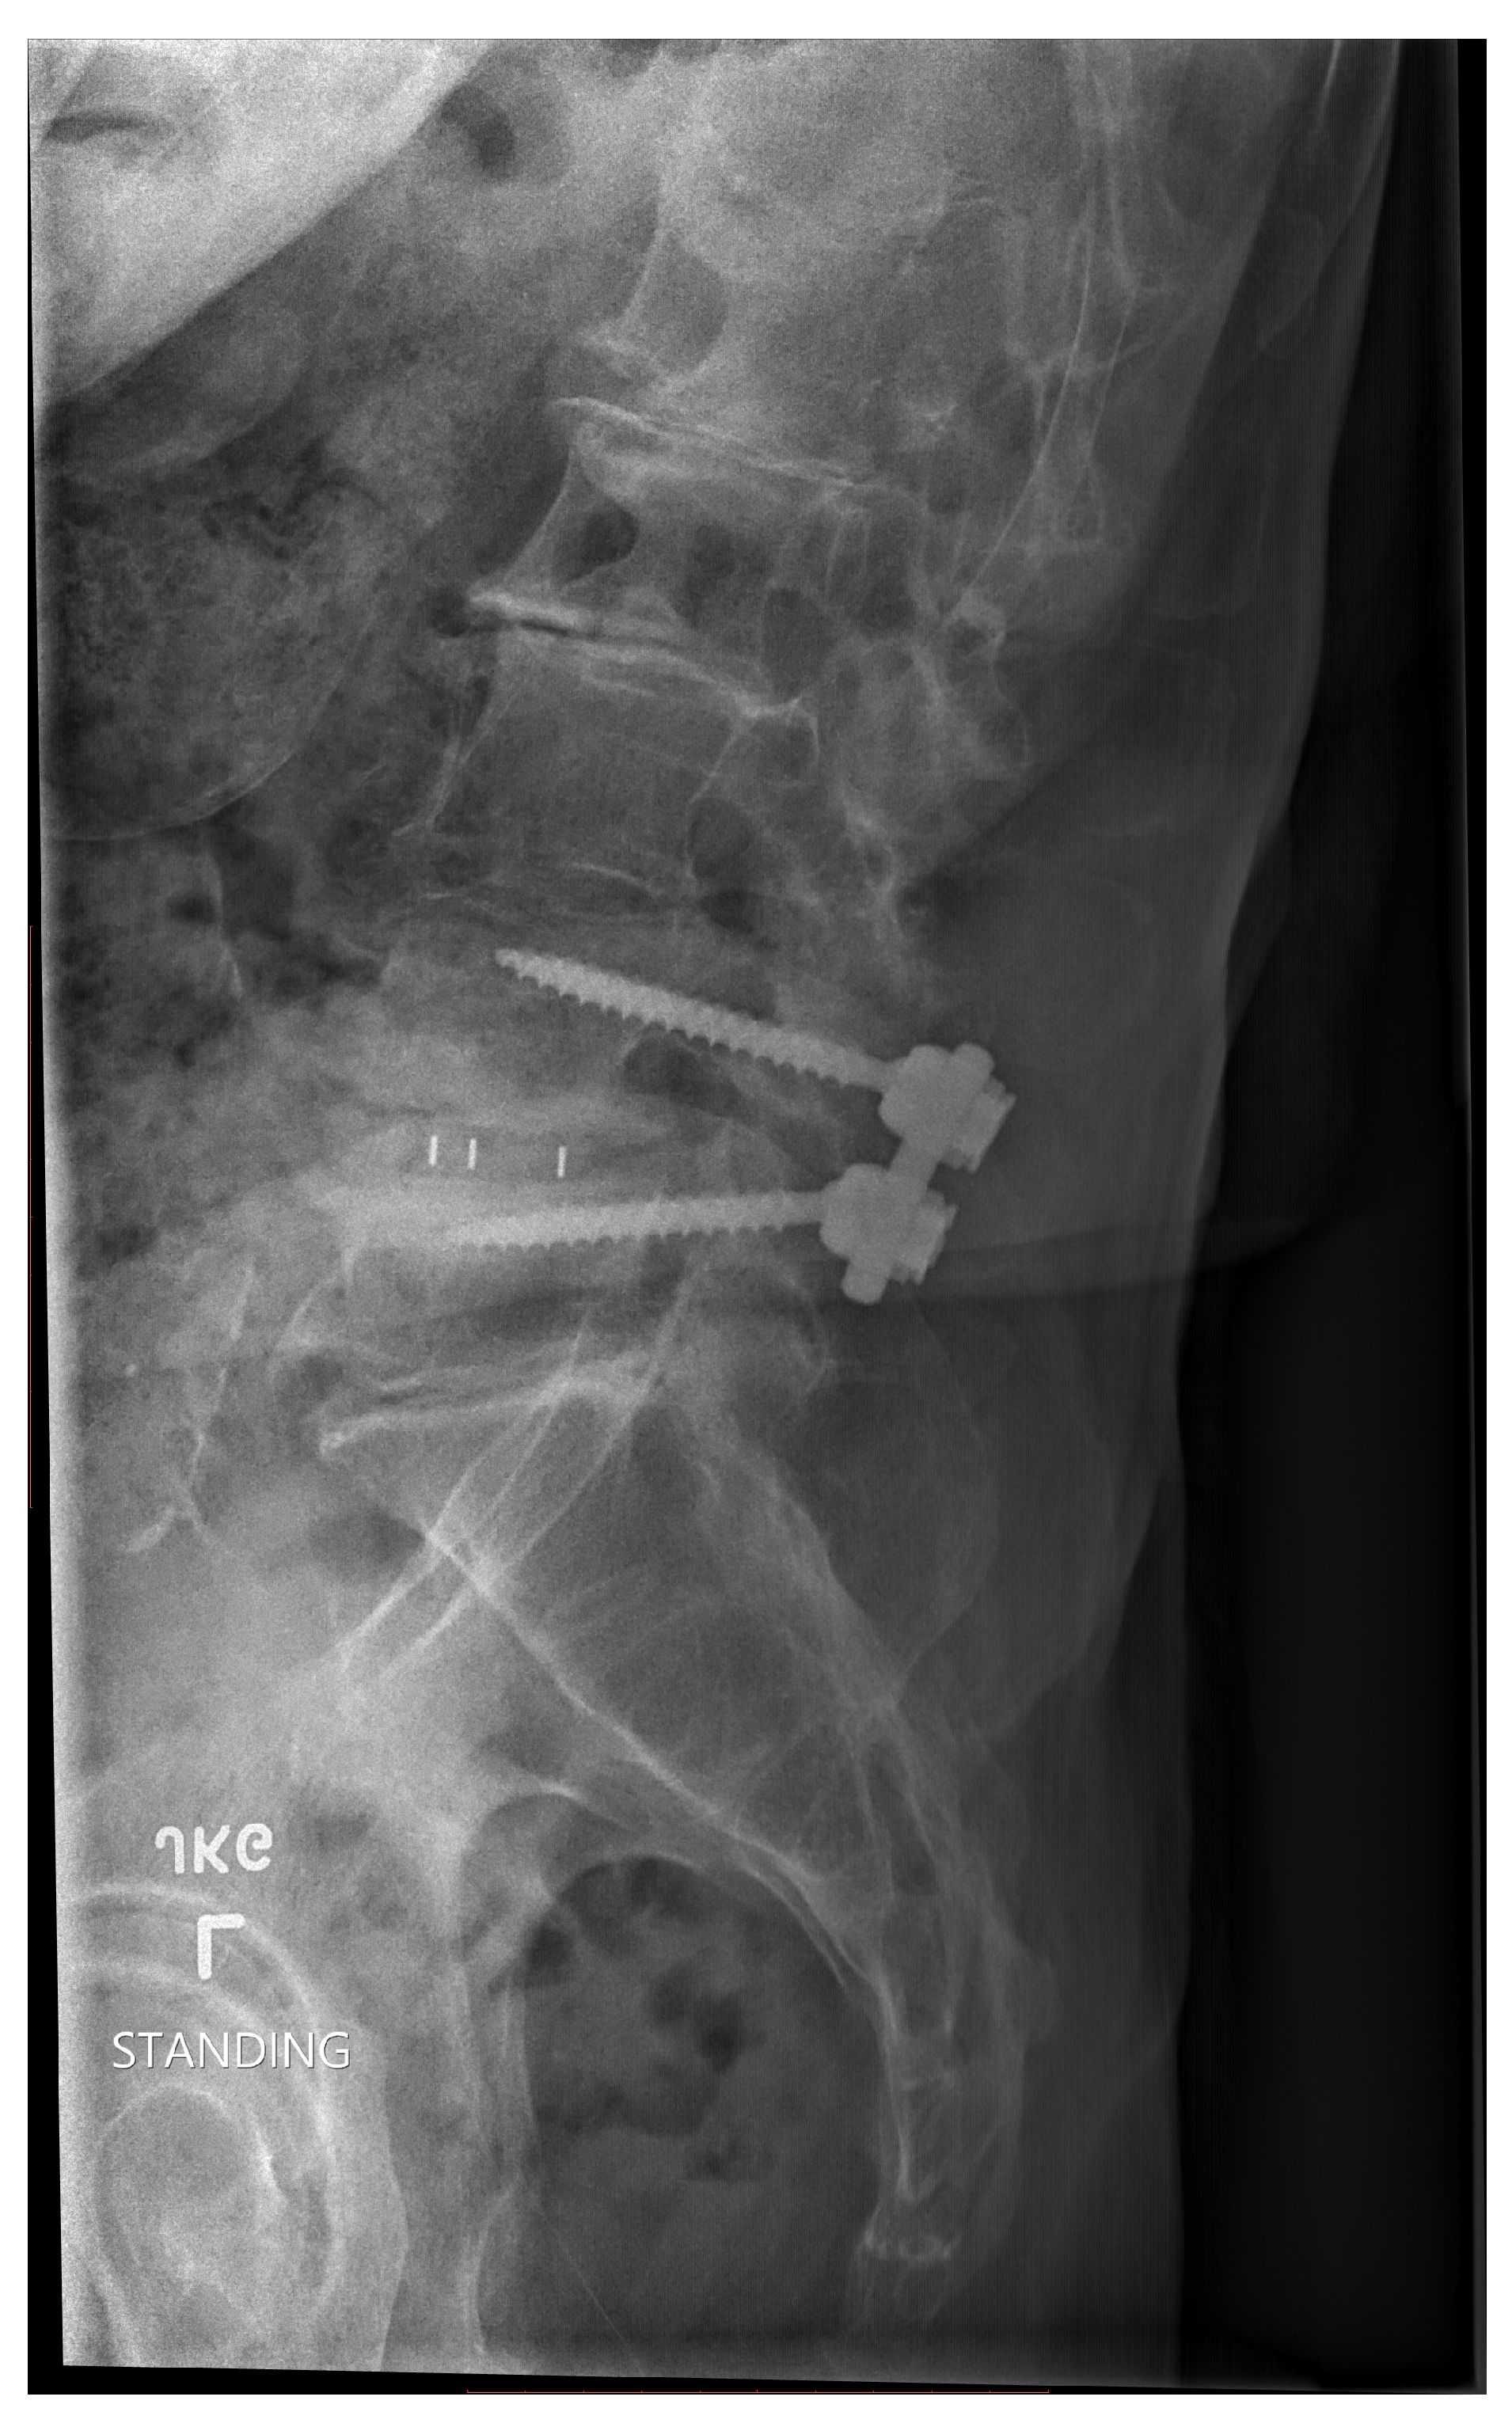

Figure 2. Post Spinal Lumbar Surgery

Figure 2: Post Lumbar Surgery

During spine fusion surgery, 1cc formable cellular bone (personal message surgeon) was installed at Kaiser Oakland Hospital. Subsequently, with the use of AI skills, the patient documented his path from jogging, epidurals, to surgery. Data collected from a self-assessment questionnaire was entered using Python code to create a dictionary (Table 1).